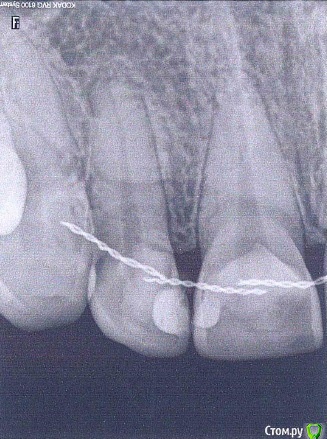

Shatalova Опубликовано 10 ноября, 2015 Поделиться Опубликовано 10 ноября, 2015 Уважаемые специалисты, прошу вашего совета в диагностике и определении дальнейшей судьбы зуба.Проблема с правым верхним резцом.Около года назад появилась чувствительность зуба на холодный воздух. Спустя некоторое время были замечены болезненные ощущения при надавливании на десну над зубом. Вне воздействия ничего не болит.Вердикт терапевта: проблема не очевидна, следить за динамикой в течение полугода.Спустя полгода.Ощущения те же: чувствительность на холод, боль при надавливании на десну.На снимке ничего нового. ЭОД:11: более 130 мка12: 2мка21: 2 мка.По словам врача, зуб мертв, его нужно вскрывать и вычищать. В прикорневой части уже воспаление, поэтому болит при надавливании. На мой вопрос, как может мертвый зуб продолжать чувствовать, врач сказал, что это есть чувствительность соседних зубов. Но это не так!Что с зубом? Что с ним дальше делать?Заранее огромное спасибо.(Снимок в приложении) Ссылка на комментарий

red_butler Опубликовано 10 ноября, 2015 Поделиться Опубликовано 10 ноября, 2015 Эод в вашем случае может врать из за ретейнера, нужно провести термопробы хладагентом 4 Ссылка на комментарий

Гарриевич Опубликовано 10 ноября, 2015 Поделиться Опубликовано 10 ноября, 2015 Эод в вашем случае может врать из за ретейнера, нужно провести термопробы хладагентомПлюсую за холод, по снимку в данном случае не определить Ссылка на комментарий

carloss Опубликовано 10 ноября, 2015 Поделиться Опубликовано 10 ноября, 2015 (изменено) в редких случаях даже тест на холод может давать положительную реакцию - некоторые нервные волокна могут долго сохранять чувствительность даже при мертвом зубе.. но навряд ли у вас этот случай, скорей всего верхушка корня выдвинулась вестибулярно через кость, после ортодонтии Изменено 10 ноября, 2015 пользователем carloss Ссылка на комментарий

carloss Опубликовано 11 ноября, 2015 Поделиться Опубликовано 11 ноября, 2015 "Верхушка корня выдвинулась вестибулярно через кость" - в переводе на обывательский это что означает? И что показано в данном случае?Ничего страшного не означает, тактика выжидательная - в редких случаях может привести тоже к депульпированию(удалению нерва). Это одна из возможных причин, которую стоит исключить или подтвердить, чтобы поставить правильный диагноз. КТ может помочь. Ссылка на комментарий